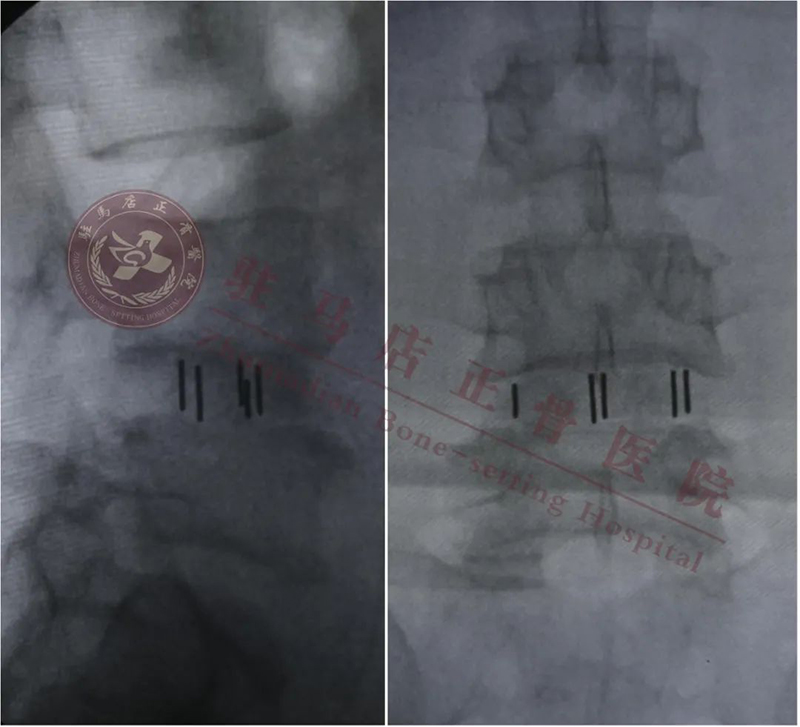

术后影像